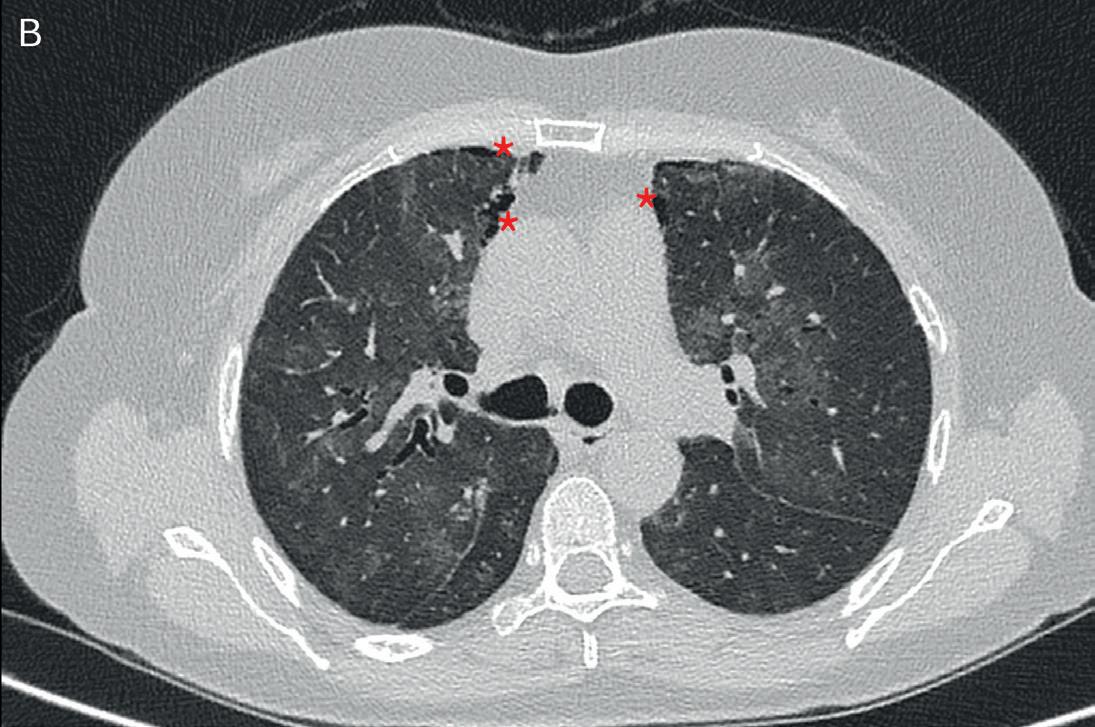

Figura 1. Plurimi infiltrati polmonari manifestazione di alveolite emorragica in un paziente con MPA (figura 1 A,B).

Presenza di bronchiectasie e iniziali cisti subpleuriche (asterischi figura 1B)

A quel punto è stata eseguita una tomografia computerizzata (TC) del torace che ha rivelato la presenza di plurime aree di opacità a vetro smerigliato senza un gradiente apico-basale evidenti in tutti i campi polmonari, con associate bronchiectasie e pseudocisti subpleuriche nelle porzioni anteriori del lobo medio (Figura 1). Per escludere un’eziologia infettiva, sono stati ese -